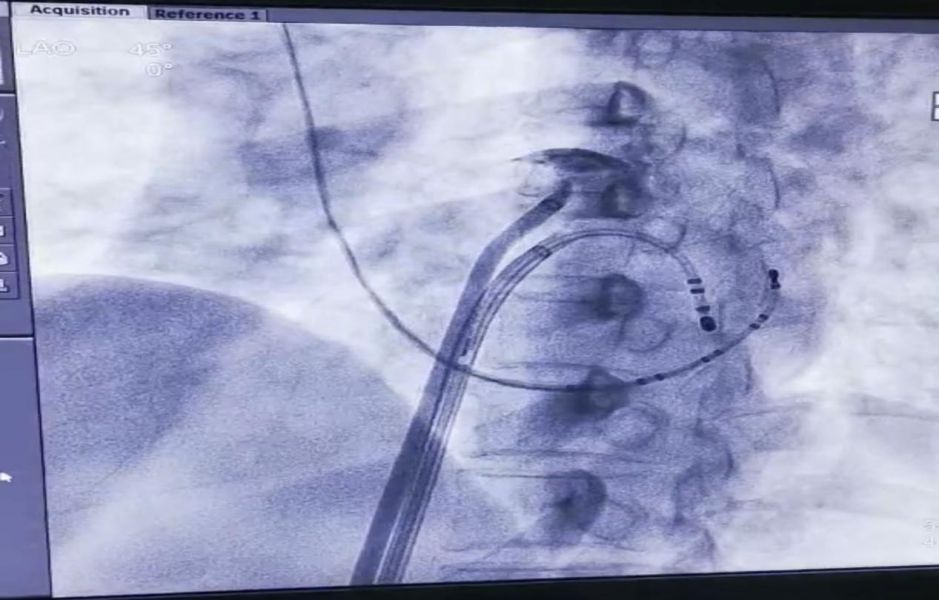

心内三科医生在为房颤患者行房颤射频消融术

穿房间隔后于右肺静脉造影